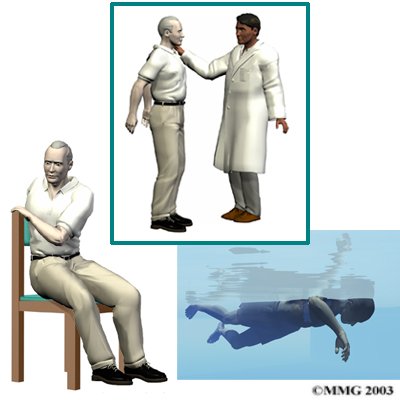

Diagnosis begins with a complete history and physical examination. Your doctor will ask questions about your symptoms and how your problem is affecting your daily activities. These include questions about where you feel pain, if you have numbness or weakness in your arms or legs, and if you are having any problems with bowel or bladder function. Your doctor will also want to know what positions or activities make your symptoms worse or better.

Then the doctor examines you to see which back movements cause pain or other symptoms. Your skin sensation, muscle strength, and reflexes are also tested.

As patients recover, they gradually advance in a series of strengthening exercises. Aerobic exercises, such as walking or swimming, can ease pain and improve endurance.

As patients recover, they gradually begin doing flexibility exercises for the hips and shoulders, and mobility and strengthening exercises to address the back muscles. Patients may also work with the physical therapist in a pool. Patients progress with exercises to improve endurance, muscle strength, and body alignment.